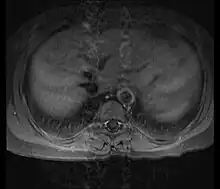

Diagnosis is based on the demonstration of vascular lesions in large and middle-sized vessels on angiography, CT scan, magnetic resonance angiography or FDG PET.[12] Seeing abnormal diffuse arterial wall thickening, the 'macaroni sign', with ultrasound is highly suggestive of the condition.[13] FDG PET can help in diagnosis of active inflammation not just in patients with active Takayasu arteritis prior to treatment but also in addition in relapsing patients receiving immunosuppressive agents.[5][14]

Contrast angiography has been the gold standard. The earliest detectable lesion is a local narrowing or irregularity of the lumen. This may develop into stenosis and occlusion. The characteristic finding is the presence of "skip lesions," where stenosis or aneurysms alternate with normal vessels. Angiography provides information on vessel anatomy and patency but does not provide information on the degree of inflammation in the wall.[12]